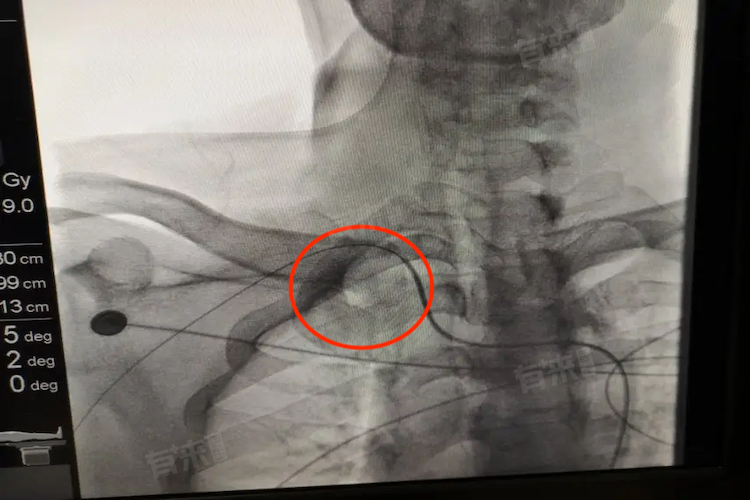

主动脉迂曲是指主动脉在解剖上出现的先天或后天性改变,导致其管腔出现曲折、延长的情况,通过医学影像学检查,如X光片或CT扫描,可以清晰地观察到主动脉的走行不再直顺,而是呈现出曲折或延长的形态。